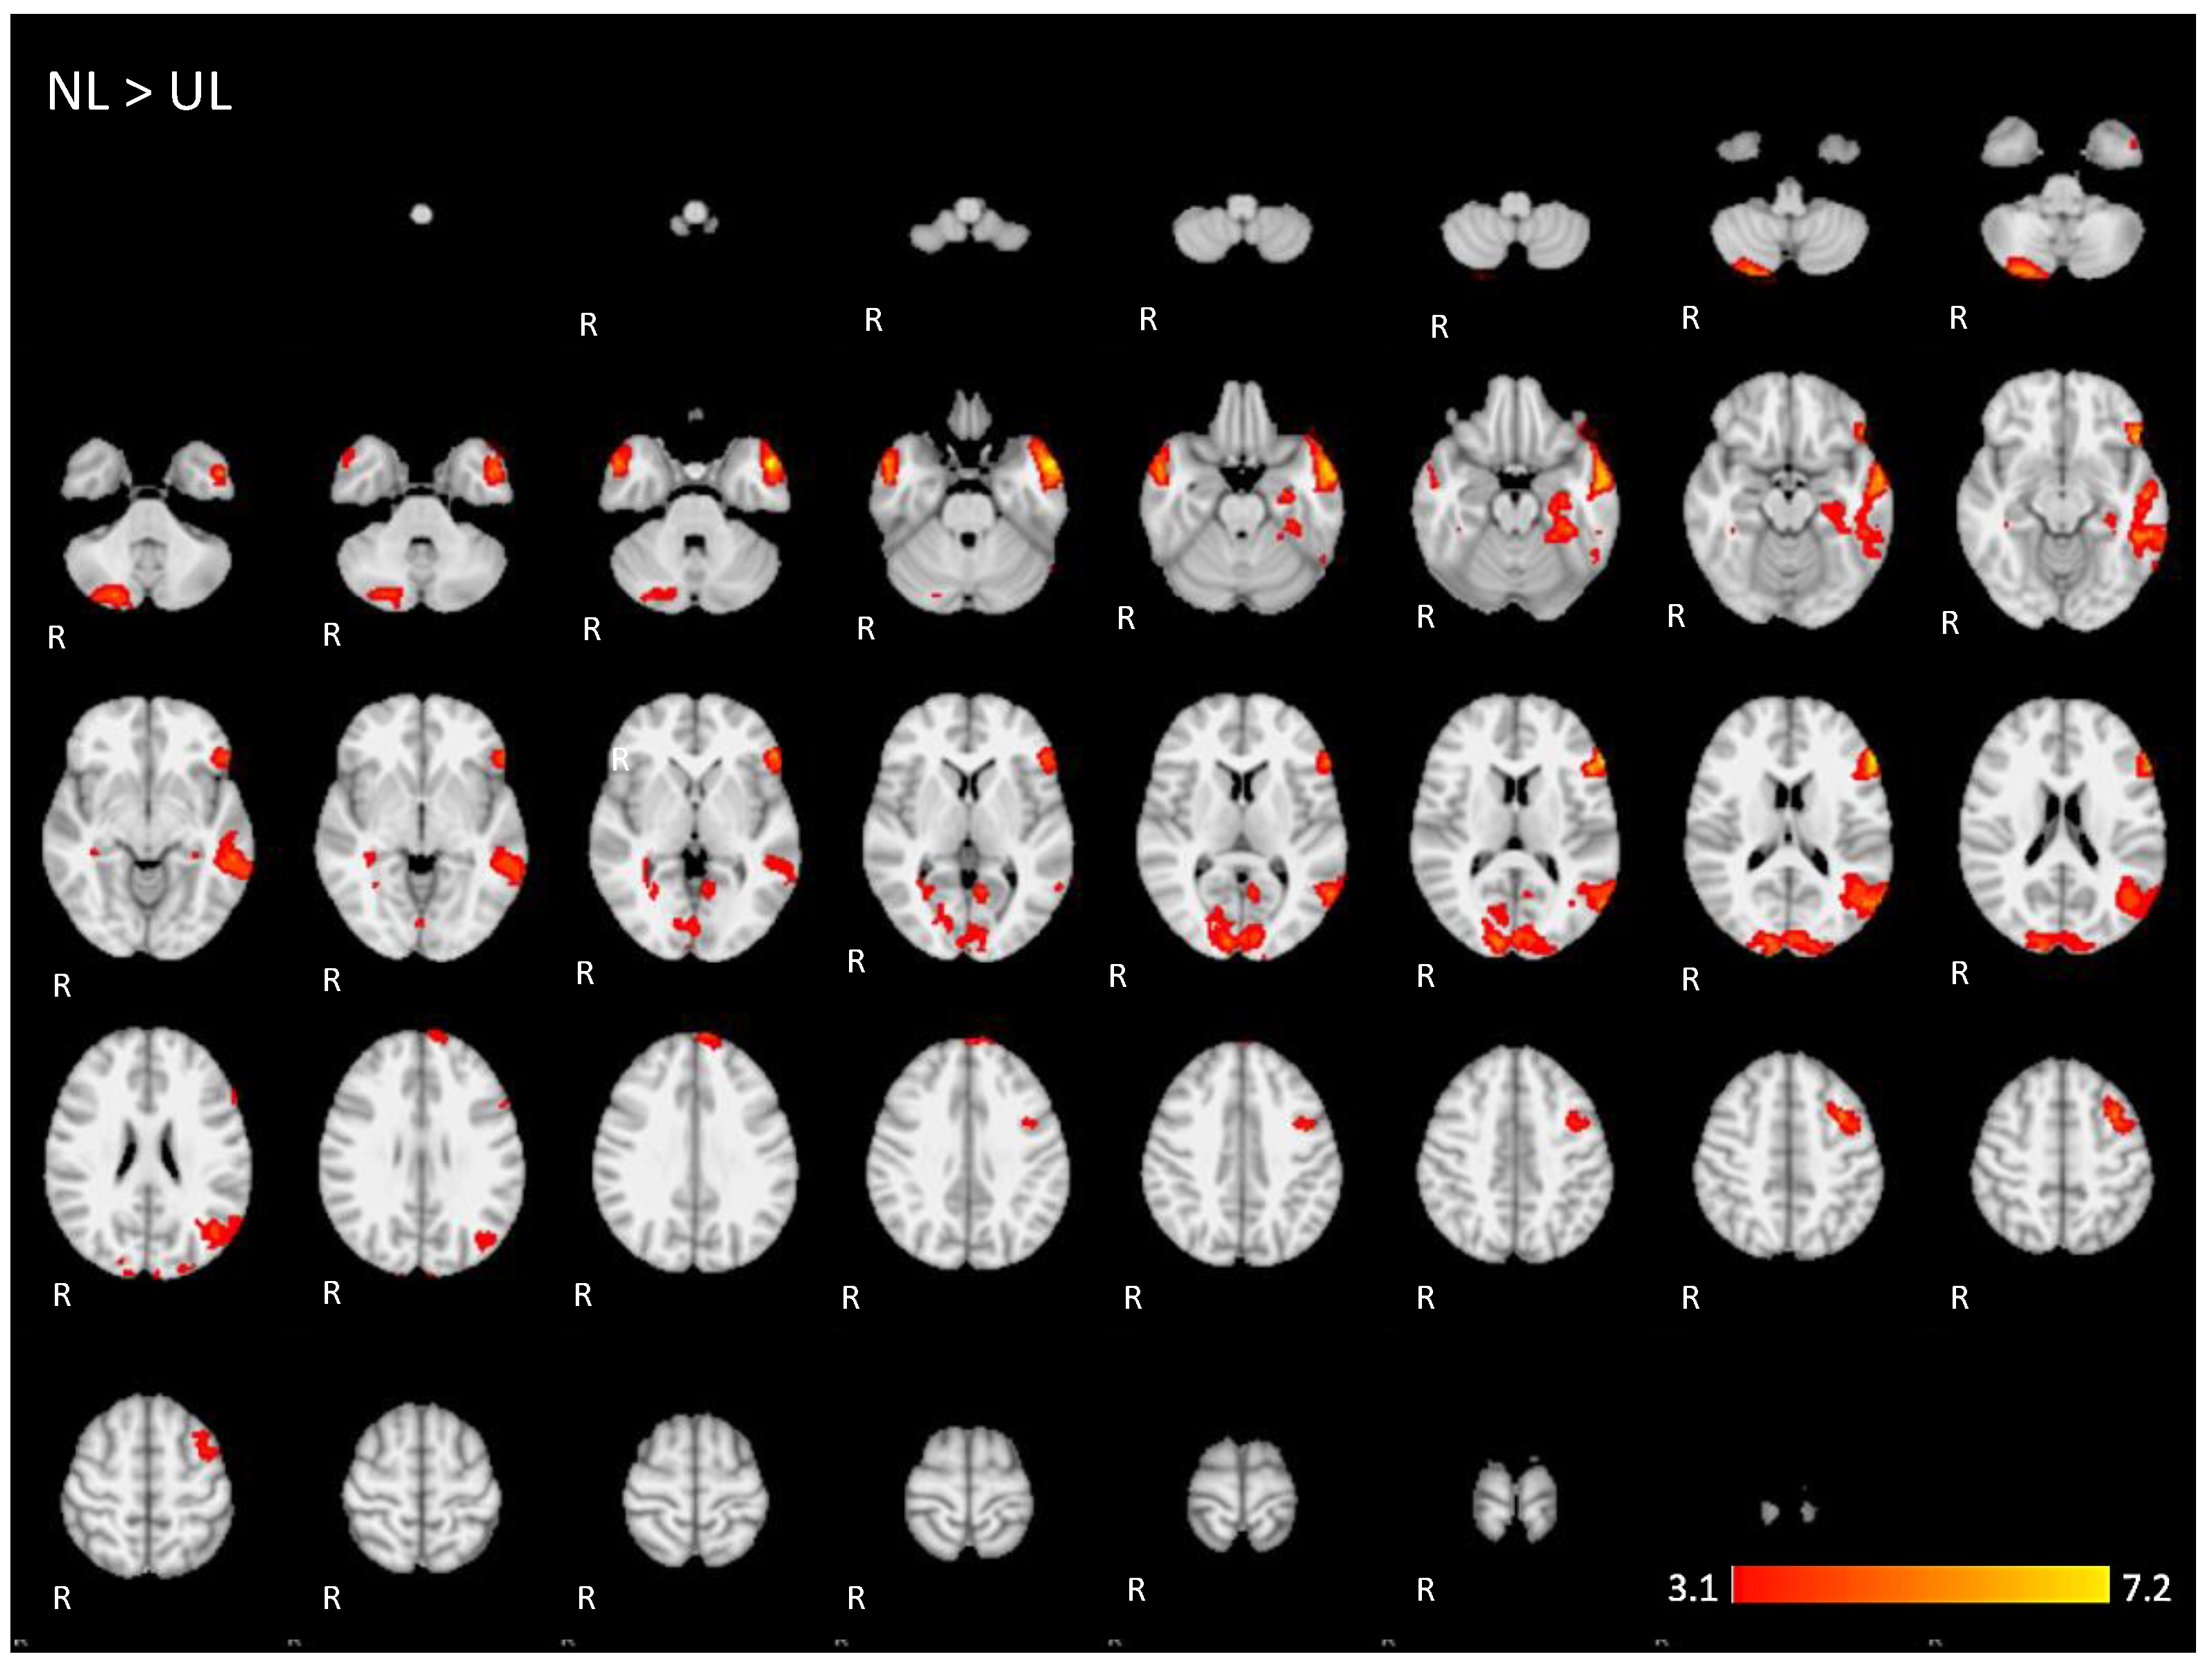

Appendix A. The 2D fMRI Maps of All Brain Slices for Both Active Conditions (NL, UL) and for Both Contrasts (NL > UL and UL > NL)

| NL > UL | 6.47 | −58 | 28 | 14 | Left inferior frontal gyrus, pars triangularis |

| 4.93 | 14 | −92 | 14 | Right occipital lobe/cuneus | |

| 4.72 | −56 | −70 | 14 | Left middle temporal gyrus | |

| 5.01 | 26 | −82 | −46 | Posterior lobe of right cerebellum | |

| 4.87 | −36 | 8 | 48 | Left middle frontal gyrus | |

| 5.33 | 54 | 0 | −26 | Right middle temporal gyrus, anterior division | |

| 4.36 | −6 | 62 | 34 | Left superior frontal gyrus | |

| 4.14 | −6 | −58 | 6 | Left precuneus cortex | |

| 3.98 | 34 | −36 | −2 | Right hippocampus | |